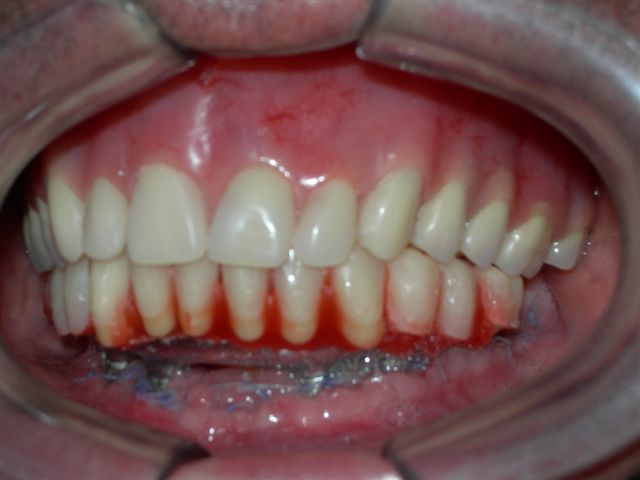

| Próteses antagonistas (VISTA DIREITA) |

Próteses antagonistas (VISTA ESQUERDA) |